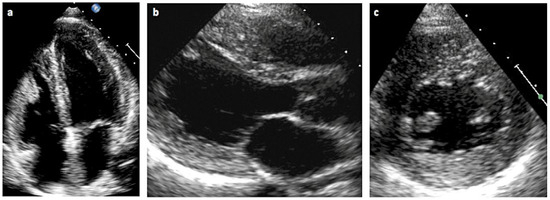

Kardiomyopathie bei Morbus Fabry

by Simone Müller, Felix C. Tanner, Christiane Gruner, Frank Ruschitzka, Andreas Flammer and Albina Nowak

Cardiovasc. Med. 2018, 21(9), 212; https://doi.org/10.4414/cvm.2018.00578 - 19 Sep 2018

Fabry disease – a rare but important cause of left ventricular hypertrophy. Fabry disease (synonym: Morbus Fabry, Anderson Fabry disease) is an Xlinked lysosomal storage disease due to a deficient activity of alpha-galactosidase A. This leads to pathological glycosphingolipid metabolism, resulting in deposition [...] Read more.

Fabry disease – a rare but important cause of left ventricular hypertrophy. Fabry disease (synonym: Morbus Fabry, Anderson Fabry disease) is an Xlinked lysosomal storage disease due to a deficient activity of alpha-galactosidase A. This leads to pathological glycosphingolipid metabolism, resulting in deposition of glycosphingolipids in lysosomes and body fluids. There is evidence that the glycolipids also accumulate extralysosomally, which is a very important factor in the pathogenic impact. Cardiac involvement is one of the most important disease manifestations because the patients mainly die from cardiac complications. There are two phenotypes: classic and later-onset. First symptoms of the classic phenotype occur during the childhood and include angiokeratomas, hypohidrosis, cornea verticillata, and tortuosity of conjunctival and retinal vessels. Young patients typically suffer from acroparaesthesias, abdominal cramping and pain crises. With advancing age, the progressive sphingolipid deposition, particularly in the endothelial cells, cardiomyocytes and podocytes, leads to arterial hypertension, cardiomyopathy, nephropathy and premature strokes. In contrast to the classic phenotype, patients with the later-onset phenotype lack the early disease symptoms. They typically present to the hospital in adulthood with cardiomyopathy or with nephropathy. In females, alpha-galactosidase A activity can range from low to normal owing to random X-chromosome inactivation. Generally, females have a milder phenotype because of the second, unaffected X-chromosome. Patients with Fabry cardiomyopathy suffer from left ventricular hypertrophy, conduction abnormalities and valvular involvement, as well as from diastolic and/or systolic heart failure symptoms. The enzyme activity determination in leucocytes is diagnostic in males but can be misleading in females owing to random X-chromosome deactivation. Thus, genetic testing is suitable for the diagnosis in females and should also be performed in males for the confirmation of the diagnosis. Since 2001, intravenous enzyme replacement therapy has been available for the treatment of patients with Fabry disease. Since 2016, oral pharmacological chaperone therapy has been available for patients with amenable mutations. Substrate reduction and gene therapies are currently in development. Full article

Show Figures

Figure 1